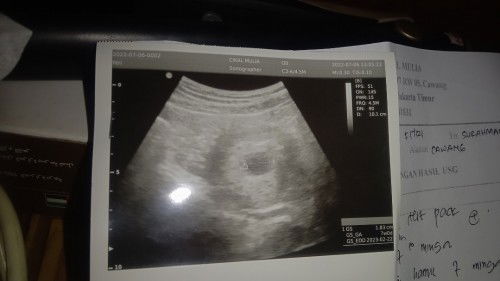

Aku di tanggal 6 juli 2022 keluar darah flek tapi cuman 1 hari doang, waktu keluar pendarahan saya langsung ke klinik saya USG, yang kelihatan masih kantung nya belom ada janin nya, dokter saran saya minum obat penguat kandungan sedalam 1 minggu, saya di suruh datang lagi paling cepat 2 minggu, paling lama 1 bulan, karna saya pengen cepat akhir nya saya datang lagi ke klinik tanggal 20 juli 2022, dokter USG lagi hasil nya bagus, janin nya sudah kelihatan dan detak jantung nya sudah kedengaran, detak jantung nya normal, alhamdulillah semua baik baik aja, tapi.... Di tanggal 21 juli 2022 jam 10 mlm aku keluar lagi flek darah cuman sedikit, saya wa bidan fitri saran nya coba minum obat penguat kandungan lagi yang di kasih dokter, terus saya wa klinik yang saya biasa USG, dokter nya tlvn kata nya sebaik nya di USG lagi biar tau hasil nya supaya di kasih resep obat nya, terus saya bilang tapi kata bidan fitri saya sebaik nya minum obat penguat kandungan menurut dokter gimana saya bilang, kata dokter nya saya tidak menjamin kan obat resep dari online, kalau mau kota periksa lagi dan biar kita tau permasalahan flek darah ini apa supaya kami bisa kasih resep obat nya langsung. Itu terserah ibu nya aja kata dokter nya. Sudah itu besok pagi saya cek sudah gak keluar darah lagi, bun solusi nya dong baik nya gimana??? Soal nya saya bingung mau dengar klinik apa bidan nya?? Soal nya kalau USG lagi duit kita sudah gak ada karna sudah habis buat USG kemaren, masa USG lagi saya kepikiran bun, tolong dong bun saran nya🙏🏻🙏🏻🙏🏻😭😭saya bingung bangett nih bun #bantusharing #bantujawabbunda